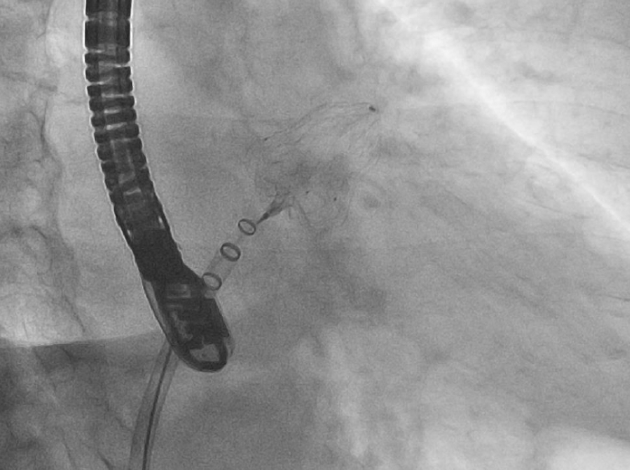

心室性不整脈に対しては、虚血性心疾患に伴う心室頻拍をはじめ、非虚血性心筋症における心室頻拍や心室細動に対し、心内膜・心外膜からのアブレーションを実施しています。必要に応じて、経皮的心膜穿刺アプローチも併用しており、複雑症例に対しても包括的な対応が可能です。また、突然死予防目的に植え込み型除細動器、心不全合併例に対しては心臓再同期療法も行っており、デバイス治療にも積極的に取り組んでいます。